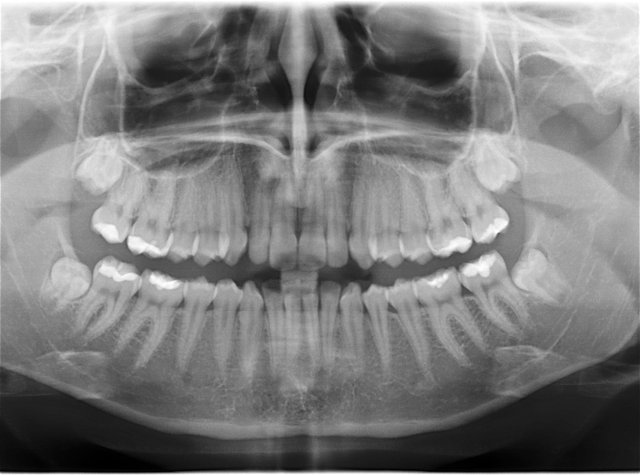

Die neuen Sensoren mit ihren hochempfindlichen Aufnahmeflächen reagieren bereits auf extrem kurze Strahlzeiten. Die Dosis reduziert sich so beim digitalen Röntgen um über 90%. Die Röntgenaufnahme erscheint in Echtzeit auf einem Monitor uns ist dank der digitalen Vernetzung in unserer gesamten Praxis einsehbar.